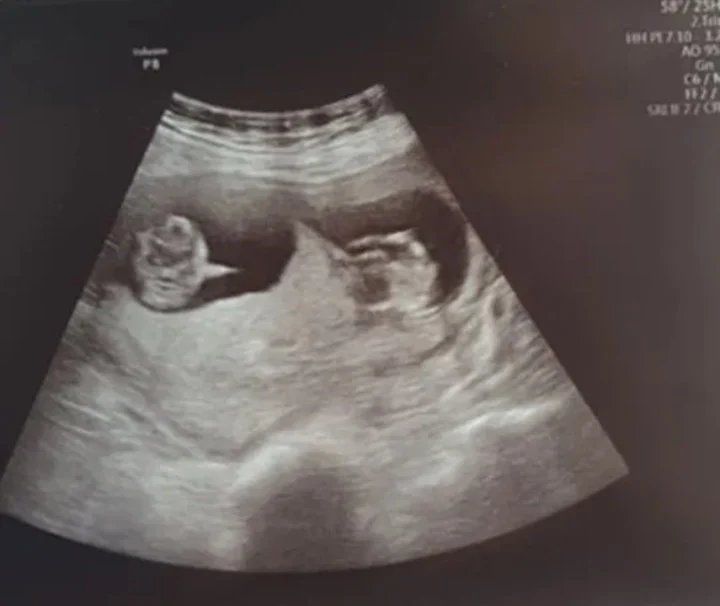

Después de diez días en coma inducido, Danielle despertó y le dijeron lo que nunca había imaginado. Esperaba gemelos. Ahora cuenta lo que sintió: "Desperté sintiéndome muy confundida y agitada por el coma, pero una vez que me recuperé del todo quedé incrédula cuando me contaron sobre los gemelos. ¡Era la guinda del pastel sabiendo que había vencido al coronavirus y que había gemelos en camino!".

Bryan agregó: "Una vez que ella estaba fuera de la UCI y en una sala, me llamó para decirme que los dos bebés estaban bien, yo dije '¿ambos?'. Al principio pensé que todavía estaba un poco confundida por todo lo que había pasado, pero me repitió gemelos sonriendo de oreja a oreja".